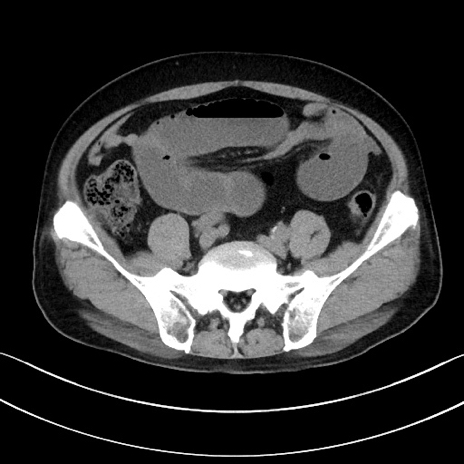

症例15(横断像)

【症例】70歳代男性

【主訴】腹痛

【現病歴】今朝から腹痛あり。全体的に痛い。特に左上の方。排ガスが今日はない。冷や汗が出る。

【既往歴】直腸癌術後

【身体所見】左側腹部〜上腹部に圧痛あり。腹膜刺激症状明らかなではない。軽度反跳痛。左下腹部に術後瘢痕あり。

【データ】WBC 7700、CRP 0.02